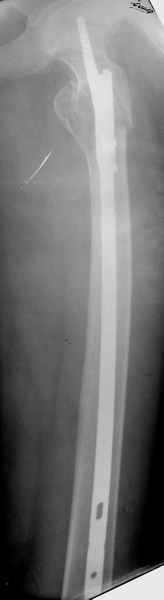

Re: Патологический перелом/ рецидив костной кисты

Спасибо за все ответы и комментарии по этому вопросу. Неделю назад мы прооперировали пациентку. Представляем ее снимки.